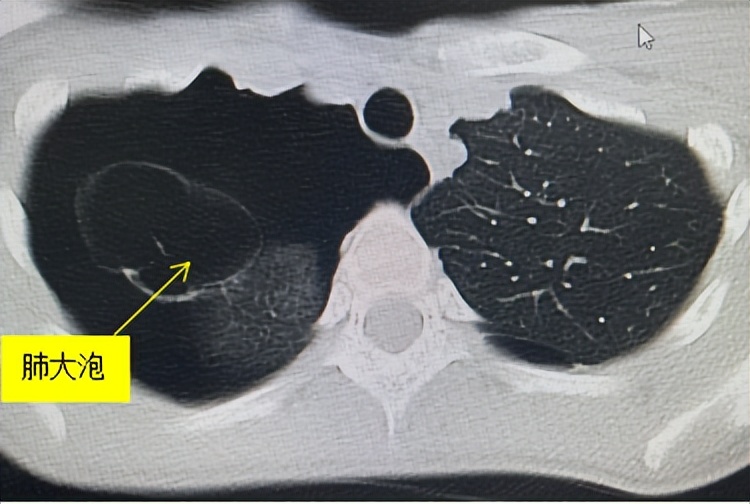

一般考虑因患者生长发育过快,易导致肺先天性弹力纤维发育不良而致肺泡壁弹性减退,扩张后容易形成肺大泡。所以长得快不一定是好事哦。

一般来讲,多发生于肺尖部,如遇胸腔压力增加则会因肺大泡破裂而致自发性气胸,特别是靠近肺边缘的肺大泡更易破裂。

气胸是胸外科最常见急诊之一,若未及时处理往往影响工作和日常生活,尤其是持续性或复发性气胸患者诊疗不及时或不当,并发肺不张、脓胸,常损害肺功能,严重者如合并血胸者也将危及生命。故怀疑为气胸者,最好是直接进行胸片、胸部CT检查,明确有无肺大泡及气胸程度,尤其是肺复张后CT更能明确肺大泡程度。

根据我们既往经验发现,气胸患者往往都会存在或大或小的肺大泡,再加上近几年胸外科微创技术的发展,临床越来越推荐手术治疗,毕竟单孔胸腔镜手术的切口小、住院时间更短、复发率更低,其优势越来越明显。